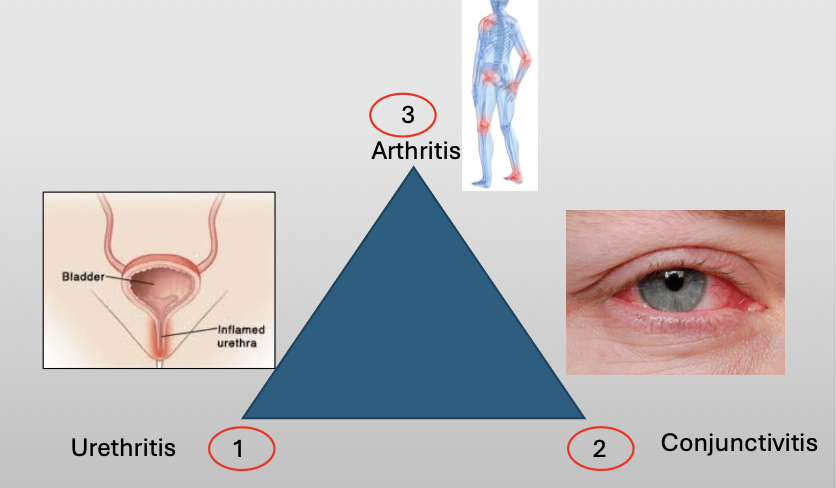

What is another name for reactive arthritis

Reiter Syndrome

What is Reiter Syndrome?

A chronic disease that classically compromises a triad of three featuers:

Urethritis

Conjunctivitis

Arthritis

What is the cause of Reiter Syndrome?

Unknown, 10% have HLA-B27

Oral lesions are 20% (nonspecific)

NSAID/AB if infection/steroids

What demographic does Reiter Syndrome show up in?

M:F (9:1)